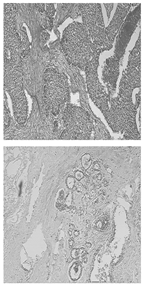

Table 11 presents a comparison between the mask images generated using three different frameworks and the ground truth masks for image segmentation. In Table 12, the performance comparison of various models on the BUSI and BreastDM datasets is presented, emphasizing their respective performance metrics. The methods for calculating performance metrics are detailed in Appendix A.

Table 11.

Comparison of different models using datasets.

For the BUSI dataset, the U-KAN model demonstrates superior performance across most metrics relative to U-Net and U-Net++. Specifically, U-KAN achieves the highest accuracy (0.933), precision (0.754), and F1 score (0.747). Additionally, it records the highest specificity (0.963) and AUC (0.935), although its recall (0.740) is marginally lower than that of U-Net++ (0.749). These results indicate that U-KAN offers balanced and robust performance, excelling particularly in accuracy and specificity, which are critical for reliable image segmentation.

Regarding the BreastDM dataset, all three models exhibit high accuracy, yet U-KAN again shows the best overall performance. U-KAN achieves the highest accuracy (0.986), recall (0.870), F1 score (0.728), specificity (0.993), and AUC (0.838). In comparison, U-Net++ demonstrates slightly lower performance with an accuracy of 0.985 and an AUC of 0.822, while U-Net exhibits an accuracy of 0.983 and an AUC of 0.815.

These findings suggest that U-KAN is particularly effective for image segmentation tasks, especially in the context of early breast cancer diagnosis. It provides superior accuracy, specificity, and balanced performance across other metrics compared to U-Net and U-Net++, thus offering enhanced capabilities for detecting early-stage breast cancer lesions. Consequently, U-KAN’s advanced performance metrics underscore its potential as a reliable model for clinical applications in breast cancer detection.